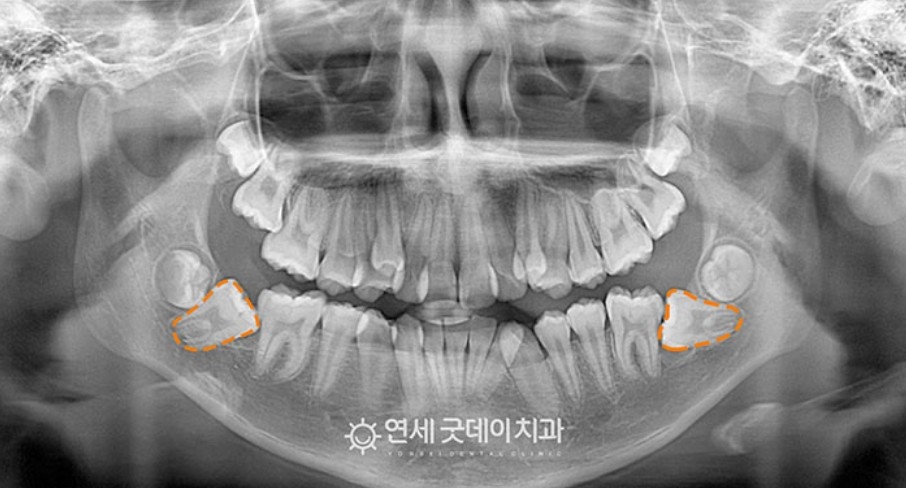

저희 병원에 찾아주신 환자분(13세 여환자)은 하악의 양측 어금니 모두 매복된 케이스라 구강외과 전문의 협진 치료로 들어갔습니다.

환자 스스로도 이러한 문제로 방문해 주셨으며, 엑스레이 촬영 후 하악 양쪽 제2 대구치가 매복되어 있는 것을 발견할 수 있었습니다.

엑스레이 사진을 보면 매복치아 형태를 볼 수 있습니다. 본래, 정상적으로 맹출되어야 하지만 온전히 누워 있고, 환자분도 별 다른 통증을 느끼지 못해 뒤늦게 인지하게 됐습니다.

구강외과 전문의와의 상의 후 발치보다는 견인하여 치아를 살리기로 결정 내렸습니다.